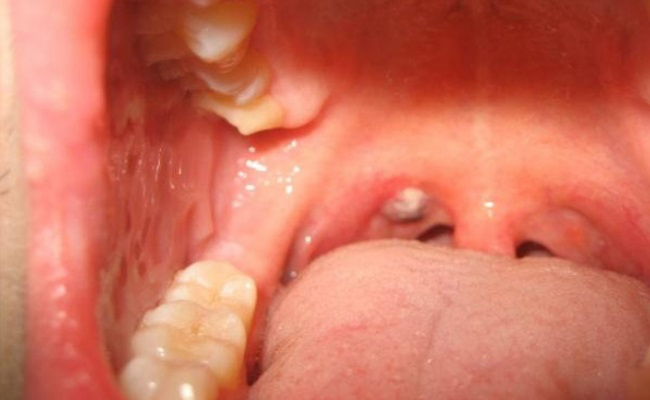

扁桃體週膿腫圖片